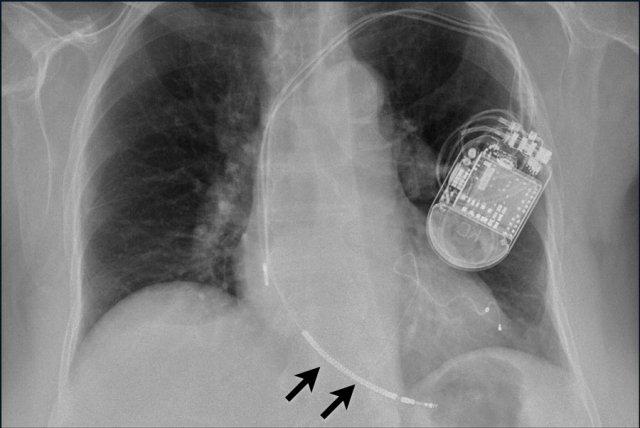

Đây là ví dụ về một ICD với các điện cực đặt tại tiểu nhĩ phải, mỏm thất phải và một điện cực đến thất trái qua tĩnh mạch vành sau.

Có thể nhận biết hai cuộn sốc điện của ICD dưới dạng các dải trắng dày hơn dọc theo đường đi của điện cực.

Đây là hình ảnh máy tạo nhịp hai thất với ba điện cực.

Điện cực tạo nhịp nhĩ phải nằm ở tiểu nhĩ phải.

Điện cực này đi xuống dưới vào nhĩ phải trước, sau đó vòng lên trên và ra trước, nơi nó được neo chặt vào các bè cơ của tiểu nhĩ.

Điện cực thất trái đi qua nhĩ phải và xoang vành, cuối cùng được đặt ở phía sau vào một tĩnh mạch tim bên trái.